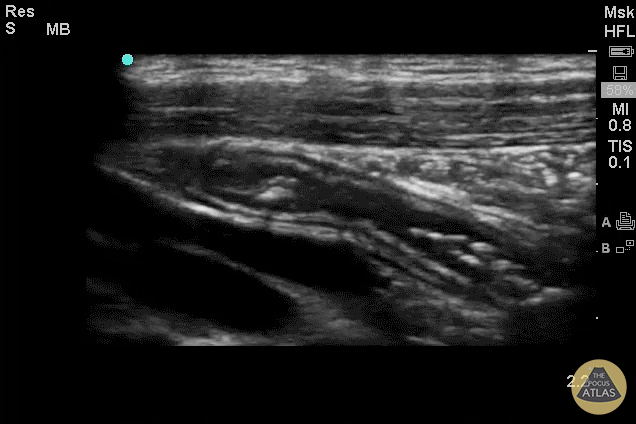

Colorized Appendicitis - 2D Appendix with Landmarks (Longitudinal)

Images provided by Sathya Subramaniam - Children’s Hospital of Philadelphia, edited by Matthew Riscinti - Kings County Emergency Medicine